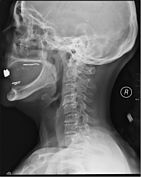

A radiographic evaluation using an X-ray, CT scan, or MRI can determine if there is damage to the spinal column and where it is located.[9] X-rays are commonly available[85] and can detect instability or misalignment of the spinal column, but do not give very detailed images and can miss injuries to the spinal cord or displacement of ligaments or disks that do not have accompanying spinal column damage.[9] Thus when X-ray findings are normal but SCI is still suspected due to pain or SCI symptoms, CT or MRI scans are used.[85] CT gives greater detail than X-rays, but exposes the patient to more radiation,[87] and it still does not give images of the spinal cord or ligaments; MRI shows body structures in the greatest detail.[9] Thus it is the standard for anyone who has neurological deficits found in SCI or is thought to have an unstable spinal column injury.[88]